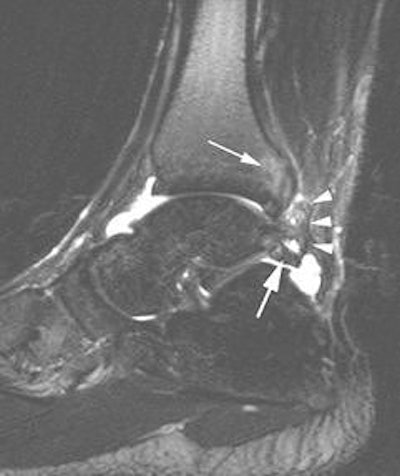

![]() |

| A 30-year-old male soccer player with clinical posterior impingement. Sagittal T2-weighted fat-suppressed MR image (TR/TE, 3,242/90; echo-train length, 9) shows os trigonum (lower arrow), joint effusion, and nodular posterolateral synovitis (arrowheads) between os trigonum and edematous posterior tibia (upper arrow). |

MR findings included posteromedial capsular thickening, tendon displacement, and posteromedial synovitis in all athletes with posteromedial impingement. Also, all posterolateral athletes had moderate to severe posterolateral synovitis. Bone marrow edema was prevent, but without specific distribution (Skeletal Radiology, February 2006, Vol. 35:2, pp. 88-94).

The focus of Robinson's most recent study, conducted with Dr. Steve Bollen from Bradford Royal Infirmary in Bradford, UK., was sonographically guided injection therapy. "We believe MRI should always be performed before injection to prevent subsequent masking of significant concomitant osteochondral or ligamentous injury," they wrote. "Our study results show a role for sonographically guided steroid and anesthetic injection into the posterolateral capsule abnormality" (American Journal of Roentgenology, July 2006, Vol. 187, pp. W53-W58).